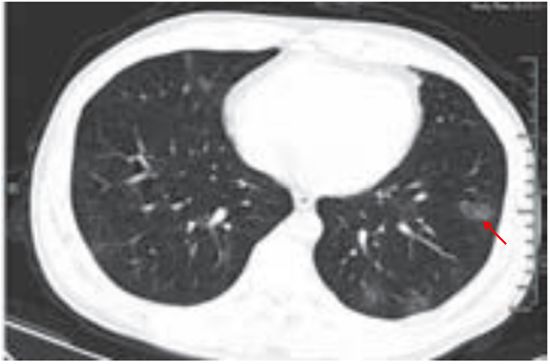

(一)曲霉菌感染

肺曲霉菌病主要是因吸入曲霉菌孢子而发病,是一种机遇性感染,为非化脓性炎症,可寄生于结核性空洞、肺癌空洞,以及慢性肺脓肿、肺囊肿、肺大疱及支气管扩张等病变所致的空洞或空腔内,少数因消化道或上呼吸道曲霉菌感染经血行播散至肺部。曲霉菌的菌丝呈游离状态,形成曲菌球。

影像学改变:

(1)典型征象为曲菌球(图 3-10)、空气半月征、手套征。

(2)多样化病灶并存,可伴有晕征、空洞、洞丝征及树上挂果征。

(3)曲菌球随体位改变而变化,球形内容物一般较光滑,密度均匀。